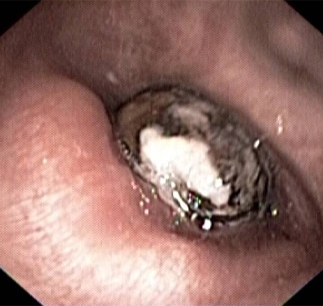

Broncoscopia para investigação de patologia endobrônquica.

[Figure caption and citation for the preceding image starts]: Imagem broncoscópica mostrando a semente de uma nêspera ocluindo completamente o brônquio intermédioDo acervo pessoal do Dr. S. Murgu e do Dr. H. Colt, Universidade da Califórnia / Irvine Medical Center [Citation ends].